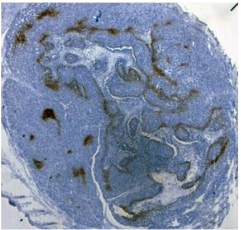

圖.福爾馬林固定的吡嘧達(dá)唑結(jié)合的免疫過氧化物酶染色

使用1:100稀釋度的FITCMAb1和1:100稀釋的辣根過氧化物酶偶聯(lián)的兔抗FITC IgG從嚙齒動(dòng)物腫瘤中切下石蠟包埋組織切片。